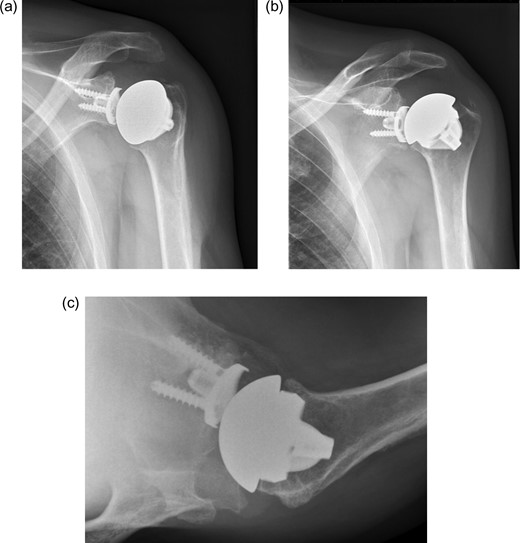

The second case is a 43-year-old female. She has alkaptonuria and chronic pain in both shoulders. Range of motion is limited in all directions. Radiologic examination shows osteoarthritis of both shoulders. MRI of the shoulder showed good condition of the cuff. A stemless total shoulder arthroplasty was performed on the left side. Peri-operative the humeral head showed obvious signs of alkaptonuria and an intact rotator cuff. (Fig. 3) One year later, a stemless cementless total shoulder arthroplasty was placed on the right side. At follow-up 2-year after left shoulder arthroplasty and 1-year after right shoulder arthroplasty patient was pain free, satisfied, and had a moderate active range of motion of both shoulders (Fig. 4). Active range of motion shows an anteflexion of 80, and an abduction of 70 on the left hand side and anteflexion of 80, and abduction of 60 on the right-hand side. Radiologic follow-up showed no signs of loosening.